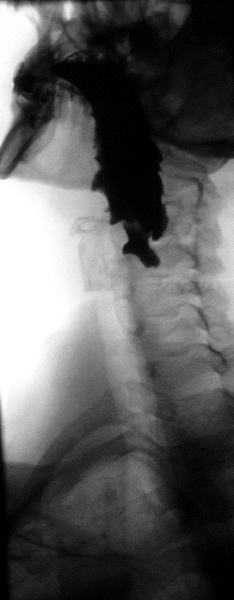

Divertículo de Zenker

Divertículo de Zenker, também conhecido como divertículo faringoesofágico, é um pseudo-divertículo[1] da mucosa da parede posterior da faringe, logo acima do músculo cricofaríngeo e abaixo do músculo constritor inferior da faringe ou do esfíncter esofágico superior (inicio do esôfago). É o divertículo mais comum do esôfago, ocorrendo geralmente após os 60 anos de idade. É decorrente da perda da elasticidade tecidual e redução do tônus muscular. O bolo alimentar deglutido exerce pressão dentro da faringe, acima do esfincter esofagiano superior, e causa herniação da mucosa e da submucosa através da área de fraqueza anatômica, proximal ao músculo cricofaríngeo.